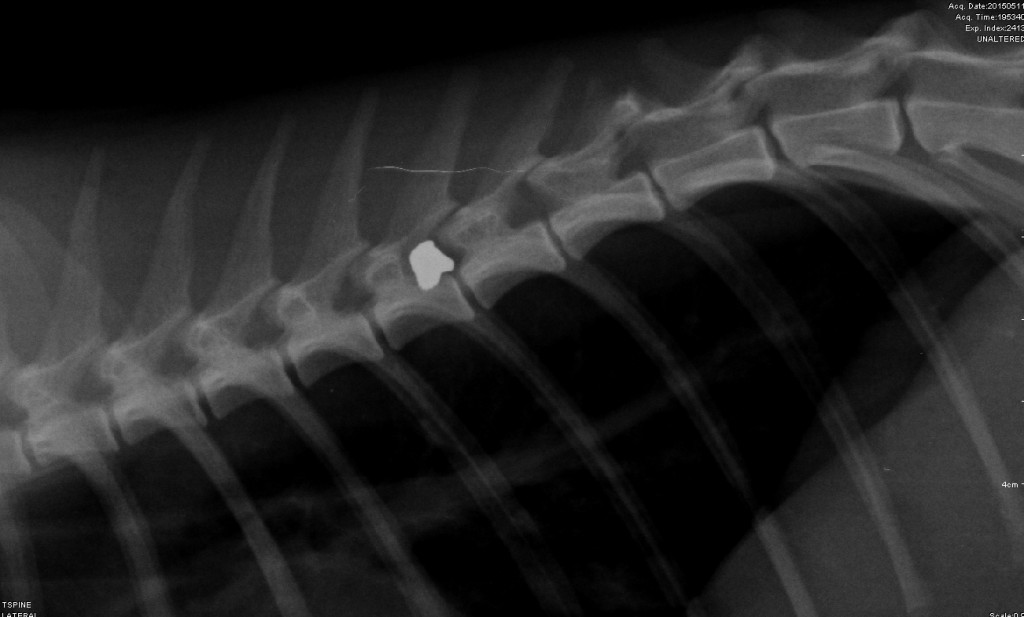

Postrzelone koty znajdowane są przy ulicy Żeromskiego. Pierwsze zawiadomienie wpłynęło 12 maja, kiedy to umierające na ulicy zwierzę zostało przewiezione do weterynarza. Niestety kota nie udało się uratować, trzeba było go uśpić. Zdjęcia rentgenowskie są dowodem na to, że śmierć zwierzęcia spowodował strzał z wiatrówki naładowanej śrutem.